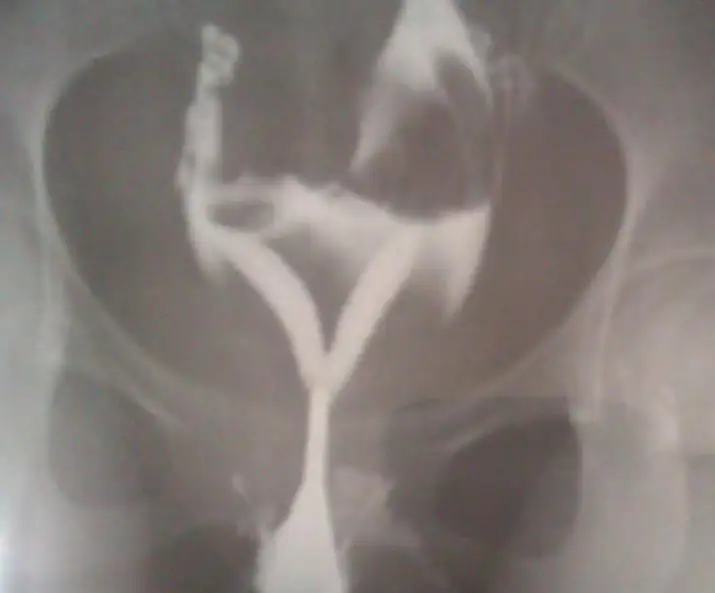

Rahim filmi ile hamile kalanlar. Rahim filminin gebelik üzerinde bir olumlu noktası olduğu bilinmekte ve bu filmi çekildikten neredeyse. Bir daha rahim filmi çektirdi ve tekrar hamile kaldı. Hsg rahim filmi çekilmesi sonrasında hamile kalanlar. Merkezimizde rahim filmi çekilenlere ilişki kısıtlaması ve gebelikten korunma önerilmemektedir.

Rahim filmi sonrası ilk 6 ay içinde özellikle ilk 2 ay içinde gebe kalma şansı çok yüksektir. Rahim içerisine tazyikli bir şekilde gönderilen sıvı yardımı ile açılması. İlk bebeği düştü 1 yıl boyunca yeniden denedi ancak yine olmadı. Gününde serephone ve inofolic kullandım 22mm yumurtam oluştu ama rahim duvarım 4mm olduğundan doktorum çatlatma iğnesi vermedi çünkü rahim kalınlığımın en az 10mm.

Rahim filmi çekildiği ay hamile kalanlar. Yani rahim filmi çektiren kişilerin gebe kalma şansının arttığı görülmüştür. Bugün aneztezi ile çaktırdim kaç gündür kendimi stres yapıp üzmekten şimdi çok ppişmanım belki aneztezi olmaran bile çekilebilirdim doktor anezteziye gerek yoktu dedi ama iyi ki öle çektirmişim korkan hanımlar aneztesi en kolay çözüm kalkınca herşey bitmiş oluyo içini rahat. Rahim filmi sonrası gebe kalan pek çok kadın vardır.

Bizim merkezimizde de deneyimlerimiz bu yöndedir. Yeğenim şu an 15 aylık. Rahim filmi hsg çektirdikten sonra hamile kalanlar. Rahim filmi aynı zamanda anne olmak isteyen kadınların tüplerinin rahim boşluğunun durumunu incelemek için yapılan röntgen filmidir biliniyor ki rahim filmi çektiren kadınların filmi çektirdikten sonra birkaç ay içinde hamile kaldığı görülmüştür.

Rahim filmi ile ilgili bilgiler ışığında hale hazırda rahim filmi çektirenler çektirdikten sonra tedavisini olanlar ankarada i̇zmirde i̇stanbulda ve adanada diğer büyük şehirlerde nasıl film çektirdiniz neler yaşadınız hangi doktoru tavsiye ediyorsunuz ya da hastahaneyi memnun kaldınız mı ücret durumu nedir. Ben de 4 sene önce evlendim geçtiğimiz yıl rahim filmi çektirmiştim lakin maalesef bende işe yaramadı. Yapılan bir çok araştırma göstermiştir ki hsg yani ilaçlı rahim filmi çekilmesi sonrasında ilk 6 ayda gebelik oranı hiç hsg çekilmeyen hastalara göre fazladır. Fakat rahim filmi çektirenler ve hamile kalanlar oldukça fazladır.

Pıhtı ya da herhangi bir nedenle tıkanmış olan tüplerin. Rahim filminden sonraki 4 ay boyunca gebe kalma olasılığının belirgin derecede arttığı çeşitli araştırmalarda defalarca tespit edilmiş bir gerçektir.